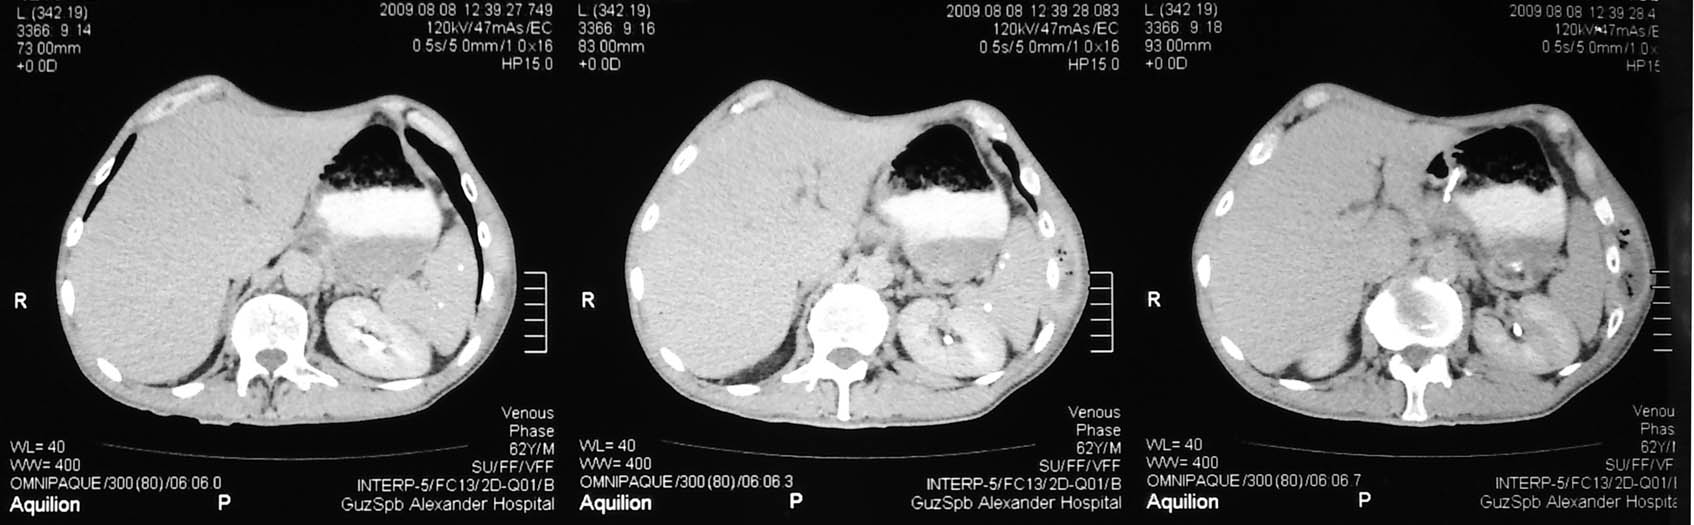

Здесь представлены КТ срезы брюшной полости и таза с контрастированием, выполненные через 2 года после травмы.

Венозная фаза

на серии кт определяются в средней трети левой почки ,латерально от ее ворот определяется гиповаскулярный участок с четкими ровными контурами .с поддавливанием чашечно-лоханочной системы,ограниченый капсулой почки ,неправильной вытянутой формы ,который в поздней венозной фазе не изменяет своей визуализации (д.д между кистой и кистозной формой почечно-клеточного рака).латерально от левой почки в мягких тканях определяется большой участок со сниженной денситометрической плотностью,размерами - 53х117мм ,с включениями газа и кольцом периферического усиления,с дренажом(вероятнее всего крупный абсцесс).печень увеличена в размере,селезенка с включениями кальция .размеры поджелудочной железы в пределах нормы,холедох и вирсунгов проток без патологии.надпочечники нормальных размеров,без изменений.в области левого тазобедреного сустава определяется участок деструкции с разрушением вертлужной впадины ,головки и шейки бедренной кости ,смещением повздошной кости вверх и латерально на 111.1мм,с фрагментом головки левой бедренной кости .в левой повздошной кости определяются гиперостоз с обширным участком остеосклероза и мелкими участками остеолитической деструкции (смешанный тип).аналогичные остеолитические изменения в крыле правой повздошной кости и в головке правой бедренной кости (сужу по 3d).по медиальному контуру средней трети тела поздошной кости определяется разрушение замыкательной пластинки с вовлечением губчатого вещества на большом протяжении,в крыше и самой вертлужной впадине с мягкотканным компонентом ,с участками пониженной денситометричской плотности (вероятнее всего участки некроза),с мелкими костными фрагментами (что косвенно может подтверждать рост изнутри снаружу),с поддавливанием на большом протяжении органов малого таза,латерально -левая стенка мочевого пузыря утолщена.вывод :такие изменения могут быть как первичного так и метастатического характера .первопричина протрузии возможно врожденного характера(дисплазия) ,затем перелом усугубил процесс(посттравматическая протрузия).меня настораживает тот момент,что изменения в повздошной кости напоминают хронический остемиелит изначально .а затем появились изменения ,сильно напоминающие озлакочествление+изолированно крупный абсцесс